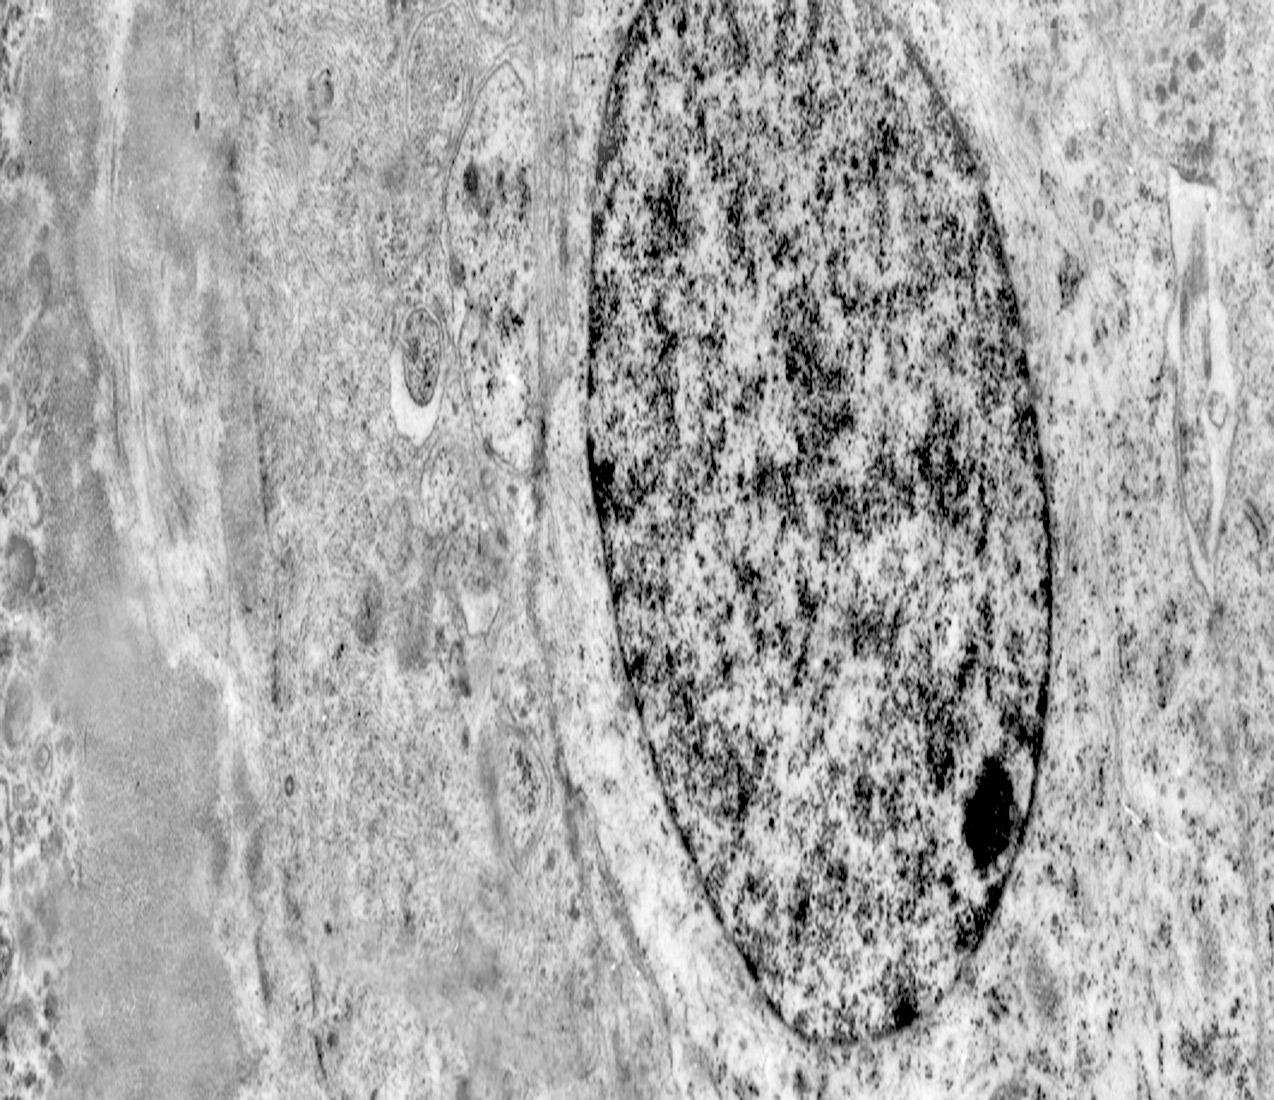

Al microscopio elettronico il citoplasma dei meningiomi meningoteliali appare ampio, ha un profilo irregolare, è fornito di prolungamenti citoplasmatici di varia lunghezza, ed è coeso alle cellule circostanti. Esso appare quasi sempre compatto anche se esibisce una densità del citosol molto variabile, fino ad immagini iperchiare, quasi trasparenti. E’ costantemente fornito di quote cospicue di organuli e di complessi proteici, e tutte queste substrutture sono distribuite in modo apparentemente uniforme nel citosol. Si evidenziano,infatti, numerosi quanto brevi segmenti di ergastoplasma rugoso, mitocondri piccoli, rotondeggianti e poveri di creste, reticolo endoplasmico liscio con cisterne ectasiche e apparentemente vuote, quote di ribosomi dispersi nel citosol, strutture di Golgi ben sviluppate, vescicole lisosomiali, numerosi microtubuli e quote variabili di filamenti intermedi variamente disposti in fascetti e orientati prevalentemente secondo l’asse maggiore della cellula. Il nucleo occupa una posizione centrale, ha un profilo irregolare, è voluminoso, è nucleolato ed ha un aspetto vescicoloso per la disposizione spaziale della cromatina lungo le fasce periferiche, a ridosso della membrana nucleare. Nel citoplasma di tali cellule si repertano in modo infrequente focolai non inerenti alla micro-architettura di tali elementi; essi sono distribuiti in modo apparentemente casuale e sono riconoscibili quali focolai di natura autofagica. Infatti, evidenziano una ultrastruttura formata da vescicole con gradi diversi di complessità e di ampiezza contenenti materiali diversi di natura biologica e organuli citoplasmatici. Su la base della complessità strutturale della loro morfologia si riconoscono focolai di microautofagia e di macro- autofagia in diversi stadi evolutivi.

1) MICROAUTOFAGIA

Nel citosol si repertano vescicole di piccole dimensioni delimitate da una membrana di contorno a mono strato. Il loro lume è occupato da materiale amorfo e da corti filamenti distribuiti in modo disordinato.

Queste vescicole sono distribuite in modo irregolare, anzi casuale e si ritrovano ad essere isolate o riunite in piccoli aggregati formando un’immagine definita corpi multivescicolari.

Frequentemente questi focolai si ritrovano commisti ad altri aventi i caratteri della macroautofagia e sono in parte da questi mascherati. A parte questi particolari reperti,il citosol è occupato da numerosi mitocondri di piccole dimensioni e di forma rotondeggiante e di aspetto compatto,da ergastoplasma rugoso e da quote ben rappresentate di reticolo endoplasmico e di strutture lisosomiali.